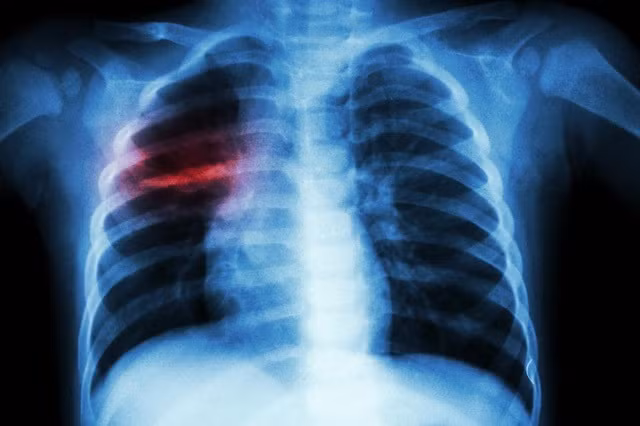

Viêm phổi là một trong những biến chứng nguy hiểm nhất của thủy đậu với biểu hiện là ho ra máu, khó thở, thở nhanh, sốt cao. Nếu không chữa trị kịp thời có thể dẫn đến tử vong.

| Một ca viêm phổi nặng do biến chứng của thủy đậu. |